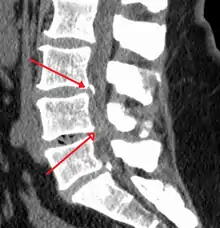

Spinal stenosis is an abnormal narrowing of the spinal canal or neural foramen that results in pressure on the spinal cord or nerve roots.[6] Symptoms may include pain, numbness, or weakness in the arms or legs.[1] Symptoms are typically gradual in onset and improve with bending forwards.[1] Severe symptoms may include loss of bladder control, loss of bowel control, or sexual dysfunction.[1]

Causes may include osteoarthritis, rheumatoid arthritis, spinal tumors, trauma, Paget's disease of the bone, scoliosis, spondylolisthesis, and the genetic condition achondroplasia.[3] It can be classified by the part of the spine affected into cervical, thoracic, and lumbar stenosis.[2] Lumbar stenosis is the most common, followed by cervical stenosis.[2] Diagnosis is generally based on symptoms and medical imaging.[4]

The diagnosis of spinal stenosis involves a complete evaluation of the spine. The process usually begins with a medical history and physical examination. X-ray and MRI scans are typically used to determine the extent and location of the nerve compression.